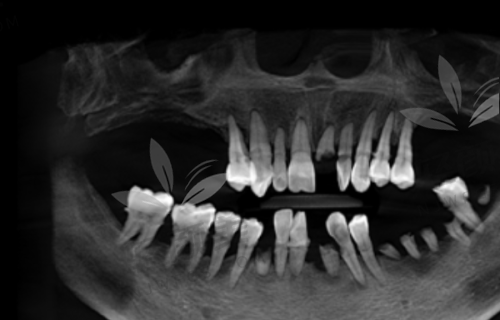

见到罗志强医生后,我一下子就放心了。罗医生特别和蔼可亲,他先是耐心地听我讲了我的牙齿情况和需求,然后给我做了详细的口腔检查。他用专精的仪器给我拍了牙片,还仔细分析了我的牙槽骨条件。罗医生说我的牙槽骨情况还不错,适合做瑞典Nobel pcc种植牙。他还跟我解释了种植牙的整个过程,包括种植体的植入、愈合期和牙冠的安装,让我对种植牙有了更清晰的认识。